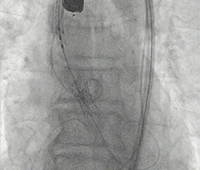

通过支撑导丝,送入23mm SAPIEN 3瓣膜,使用独特调弯功能,保证安全过弓并成功跨瓣;调整至共平面角度,瓣膜到位,快速起搏下-2cc精准释放瓣膜。

图片

+1cc体积后扩。

撤出导丝后,造影超声结果均显示瓣膜工作良好,瓣膜释放后流入/流出比例=80:20,术后导管测量压差5mmHg,经胸超声检测无周漏、无冠脉阻塞、无支架植入、无起搏器植入、无并发症,手术成功。